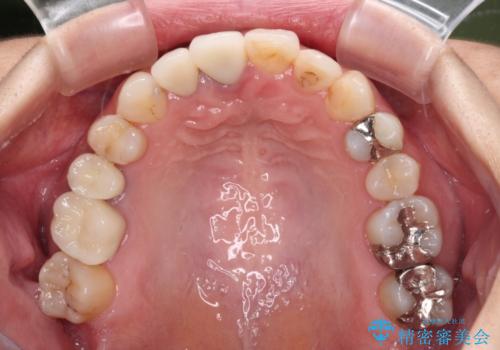

前歯のクロスバイトと治療が必要なむし歯 矯正とセラミックの総合歯科治療

- 前歯が痛いとのことで来院された患者様です。

前歯は根管治療が必要であったため、まずは根管治療を行いましたが、痛みが引いた後、矯正治療や前々から治療が必要と言われてきた歯を治療したいとのことでした。

前歯のクロスバイトはインビザラインで改善し、抜歯が必要な部分はインプラントを、その他むし歯が進行している歯はセラミッククラウンによる補綴治療することとしました。

仕事がお忙しく、インビザラインをあまりしっかりと使用できなかったようで、何とか長い期間をかけて歯列を整えることができました。

磨きにくく、何度もむし歯治療を繰り返していた前歯をスッキリと整えることができました。